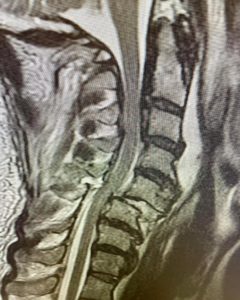

Here is an example of another cervical spine case: MRI and CT scans show a 54 year-old male who had a cervical fracture dislocation at C5-6 after diving forward into shallow water and striking his head. He was fortunate not to be paralyzed. The patient also had chronic conditions in his cervical spine that put him at even higher risk. He had severe cervical stenosis, or narrowing of the spinal canal. He also had a somewhat rare condition called OPLL or ossification of the posterior longitudinal ligament.